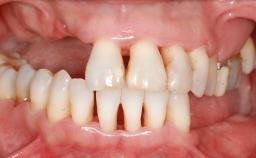

A 45-year-old woman with a completely edentulous maxilla was referred to evaluate the possibility of rehabilitation with an implant-supported prosthesis. This patient was healthy and a non-smoker. She had been wearing a maxillary complete denture opposing a natural mandibular dentition since her twenties. This situation had resulted in progressive resorption of the alveolar ridge, repeatedly creating a need for relining the denture. Twenty years later, despite multiple adaptations and the use of “glues” the denture was unstable and causing the patient psychological and functional discomfort.

Defining Characteristics Fully edentulous upper jaw to be rehabilitated with four or more implants

Bone Volume Deficient vertically or deficient vertically AND horizontally

Defining Characteristics Fully edentulous upper jaw to be rehabilitated with an implant-borne fixed dental prosthesis